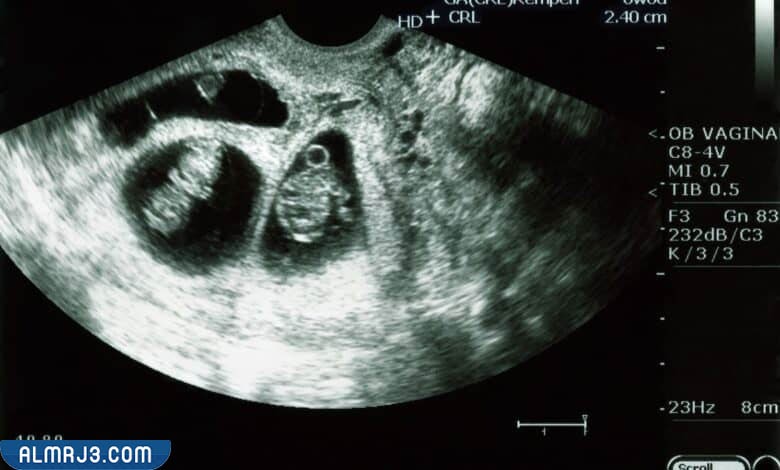

تزداد نسبة هرمون الحمل داخل الغدد التناسلية لجسم المرأة بعد التلقيح وإتمام عملية التصاق البويضة في جدار الرحم، ولكن وبعدما تذهب الأم إلى الطبيب المعالج قد يتعرف على وجود جنين داخل الرحم باستخدام الموجات فوق الصوتية، ويتم ذلك الأمر بعد انتهاء الدورة الشهرية بفترة بسيطة من الوقت قد تصل إلى الأسبوعين أو الثلاثة أسابيع، كذا ويساعد جهاز الدوبلر المخصص للكشف عن نبضات الجنين في توضيح عدد الأجنة الموجودة داخل الرحم وذلك لأنه عند الحمل بتوأم يصدر هذا الجهاز نبضات مزدوجة يستطيع الطبيب المعالج من اكتشافها بمنتهى السهولة.

- نبضات قلب مزدوجة: يبدأ الطبيب في سماع نبضات قلب الجنين للاطمئنان عليه، ولكنه قد يكتشف أن هذه النبضات مزدوجة؛ مما يؤكد وجود جنين آخر داخل الرحم.